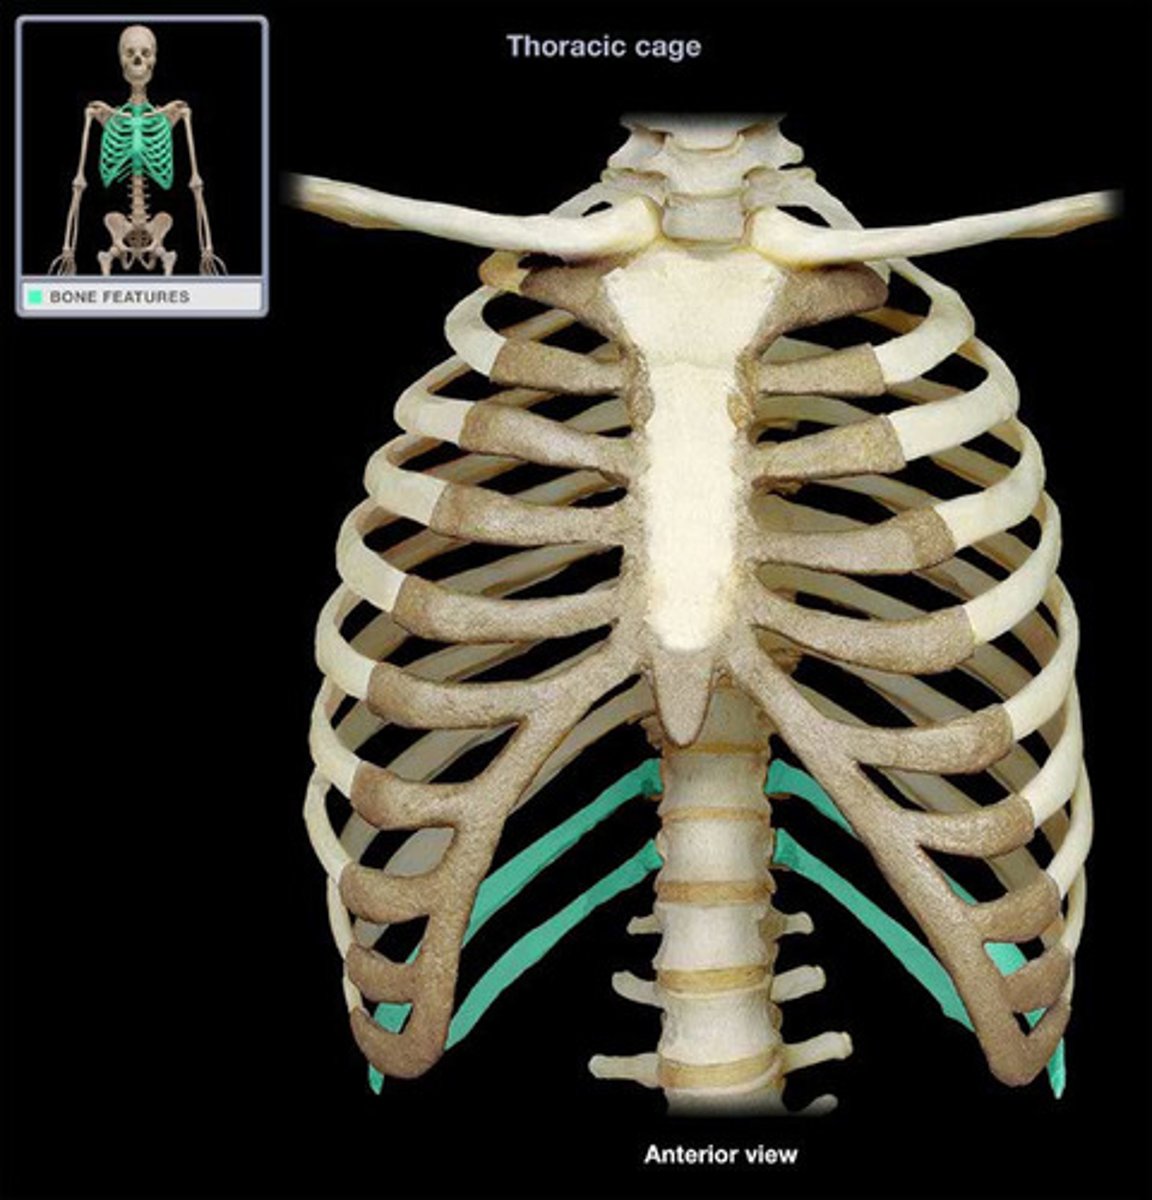

Floating Ribs

Sternum

Manubrium

Body

Xiphoid Process